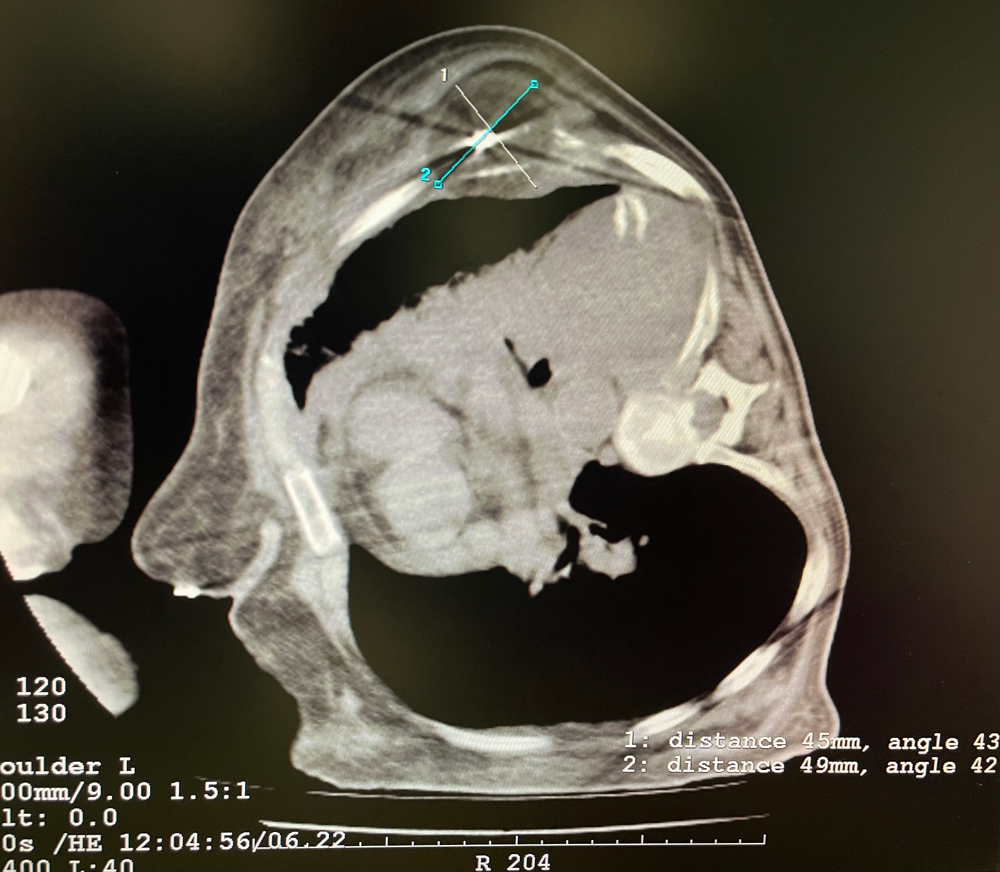

女,56歲,肺轉移瘤,骶骨、左側肋骨各一轉移灶,病灶大小均為5cm。骶骨轉移灶、肋骨轉移灶各進行2個凍融循環。患者術后狀況良好。